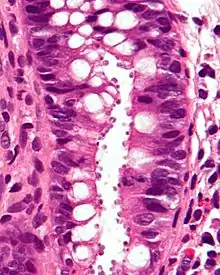

| Micrograph showing cryptosporidiosis. The cryptosporidium are the small, round bodies in apical vacuoles on the surface of the epithelium. H&E stain. Colonic biopsy. | |

Other staining techniques include acid-fast staining,[26] which will stain the oocysts red.[25] One type of acid-fast stain is the Kinyoun stain.[21] Giemsa staining can also be performed.[22] Part of the small intestine can be stained with hematoxylin and eosin (H & E), which will show oocysts attached to the epithelial cells.[25]